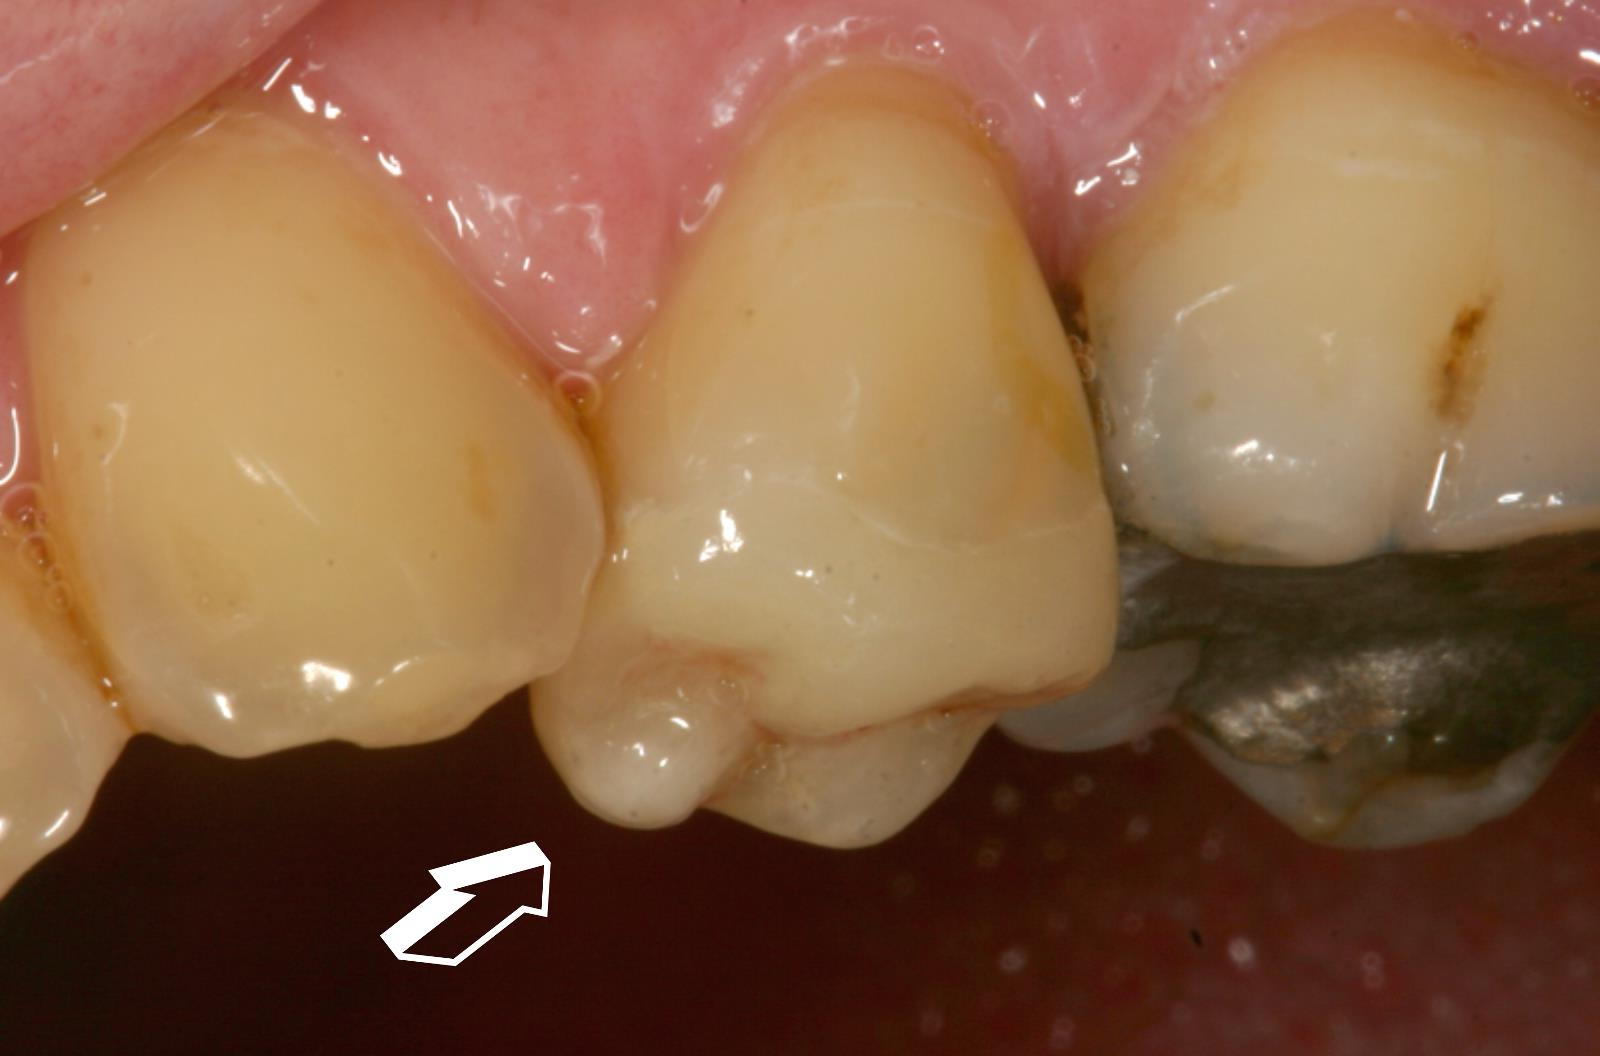

Start » Infos für Patienten » Kronen und Brücken » Teilkronen » Teilkronen in Presskeramik und Gold

Inlay in Gold, Teilkronen in Presskeramik

• Teilkrone auf dem Modell durchleuchtet.

• Presskeramik Teilkrone mit Chamäleon Effekt

• Inlay aus einer Goldlegierung, Teilkrone in Presskeramik

Teilkronen in Presskeramik und Gold

Wenn einZahn nur an der Kaufläche geschädigt ist, kann der Zahn nur zum Teil überkront werden. Es wird mehr natürliche Substanz erhalten. Teilkronen aus Keramik sind eingesetzt fast unsichtbar.